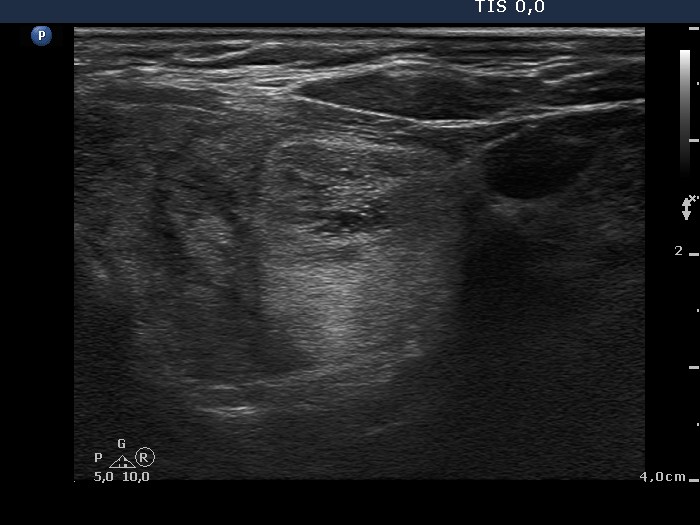

Follow-up examination 2 years later (2nd and 3rd rows of images):

Clinical presentation: the complaints of the patient worsened and requested a repeat examination.

Palpation: there was a nodule in the left lobe.

Hormonal investigation: indicated euthyroidism on daily 87.5 microgram levothyroxine (TSH-level 1.88 mIU/L).

Ultrasonography: was unchanged except for the increase of the left lobe by 38% in volume.Cytology: benign lesion.

The patient was operated on because of compression signs.

Histopathology: Hashimoto's thyroiditis and multiple hyperplastic nodules in the left lobe.